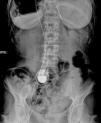

The patient reported worsening fatigue with dyspnea on minimal exertion and episodes of dizziness for three days, which had led her to visit the emergency department of her local hospital. On admission she presented an irregular pulse at 53 bpm and the ECG showed 2:1 AVB (Figure 1). Laboratory tests showed no ionic changes or thyroid dysfunction and the patient was taking no drugs that would affect atrioventricular conduction. Physical examination revealed extensive superficial venous circulation over the abdomen and chest.

An attempt at PPM implantation using conventional venous access failed due to extensive occlusion of both subclavian veins with widespread superficial and deep vein collateral circulation (Figure 2).